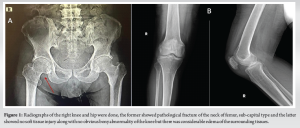

A 65-year-old male, known case of chronic kidney disease (CKD) for the past 3 years and currently undergoing hemodialysis 3 times per week, presented to the nephrology outpatient department for routine follow-up. He reported a 3-day history of difficulty lifting his right leg, along with swelling and pain in his right knee, and was referred to the orthopedics department for further evaluation. On presentation, the patient had an externally rotated right lower limb with apparent shortening, accompanied by pain and swelling in his right knee, his primary complaint. The knee pain was described as sudden in onset, progressively worsening, non-radiating, and non-referred. It was exacerbated by even minimal movement of the joint and alleviated by immobilization and bed rest. He also noted associated swelling in the knee. There was no history of trauma, fever, recent weight loss, or previous tuberculosis. The patient is also a known case of type 2 diabetes mellitus and hypertension for the past 15 years and is compliant with his prescribed medications. On examination, the right lower limb was noted to be externally rotated with an apparent shortening of approximately 0.5 cm. The knee was held in extension and exhibited diffuse tenderness and swelling, predominantly over the suprapatellar and parapatellar regions, along with a local rise in temperature. The joint appeared tense on palpation. Hip range of motion was restricted and painful, particularly with internal rotation. A straight leg raise test was possible up to 70°, though passive elevation beyond that was not feasible. Passive knee flexion was limited to 20° and was markedly painful, with active flexion not possible. The patient was hypertensive with a blood pressure of 148/92 mmHg, tachycardic at 102 beats/min, tachypneic at 22 breaths/min, and afebrile with a recorded temperature of 38.7°C. He maintained an oxygen saturation of 96% on room air. Laboratory investigations revealed a hemoglobin level of 8.4 g/dL, total leukocyte count of 8130 cells/mm3, and an elevated serum urea level of 102 mmol/L, consistent with his known CKD. Radiographic evaluation of the right hip and knee showed a pathological subcapital fracture of the femoral neck with no associated soft-tissue injury. While no definitive bony abnormalities were noted in the knee, there was significant soft tissue swelling and edema (Fig. 1).